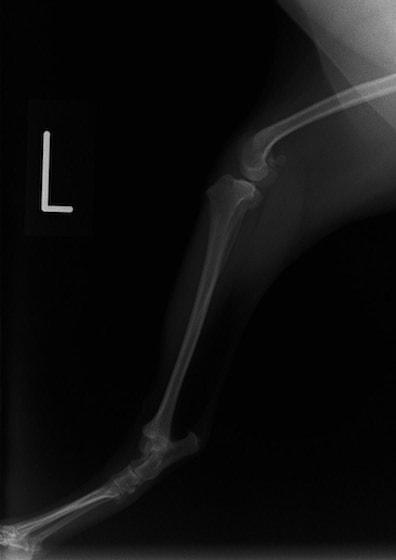

■ 症例20 ポメラニアン 8ヶ月 1.8kg

左右膝蓋骨脱臼 グレードⅢ

2ヶ月前から間欠的跛行が認められ、両膝の膝蓋骨脱臼整復術を行った。

手技は縫工筋及び内側広筋の解放、脛骨粗面の外側転位、滑車ブロック形造溝術、内外側関節包の縫縮を選択し実施した。

右側の膝蓋骨脱臼は上記手技で整復されたものの、左側はそれのみでは膝蓋骨が浮く様子が認められた。その為、PDS縫合糸にて膝蓋靱帯を1糸のみ縫合し、靱帯の縫縮を行った。

膝蓋骨脱臼は膝関節における膝蓋骨の内外側の脱臼と定義されるが、時として単純な内外の脱臼ではなく、膝蓋骨が大きく前方に浮き上がるように脱臼する場合がある。特にトイプードルやポメラニアンといった犬種に多く認められる。

内側脱臼に加えて前方への浮き上がりを矯正する為に、従来より脛骨粗面転移により膝蓋靭帯を外方と下方に引っ張り、固定する方法を選択する。膝蓋骨の前方への浮き上がりが軽度の場合は、従来法ではなく関節包の縫縮で対応していた。しかし、一部の症例で膝蓋骨の動きが悪くなり伸展機構が円滑に機能せずロボット様歩行になるケースがあった。

その為、膝蓋靭帯自体を縫縮する方法を採用した。この方法により、膝関節の伸展機構を妨げず膝蓋骨の軽度の浮きを矯正することが可能となった。

本症例の経過は良好である